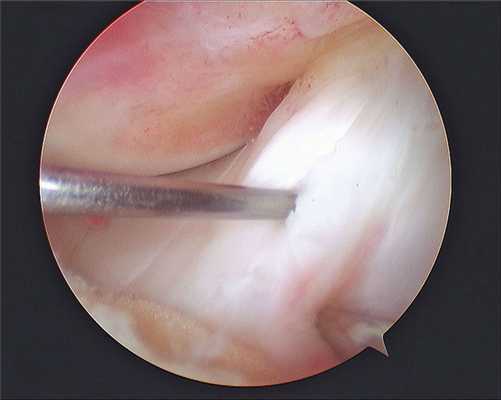

2. В ходе диагностической артроскопии подтверждается наличие дефицита (или недостаточности мениска) после выполненной ранее субтотальной или тотальной менискэктомии, оценивается выраженность вторичных хондральных изменений, которые также могут потребовать лечения, особенно в случаях, когда первичное вмешательство на коленном суставе выполнялось в другом учреждении или другим хирургом (рис. 3).